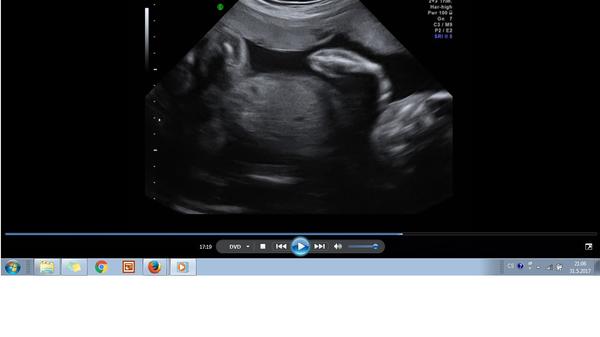

tak to jo - tak to vypadá vážně na chlapečka. Jak jsou hubený tak je maj prostě velký :D Kdyby to byla fotka z 12-13 tt tak by to vypadalo na holčičku (jednalo by se o pohlavní hrbolek který je rovnoběžný s páteří) ale v 17 to už bude pinďa , a mám dojem že vidím i varlátka.